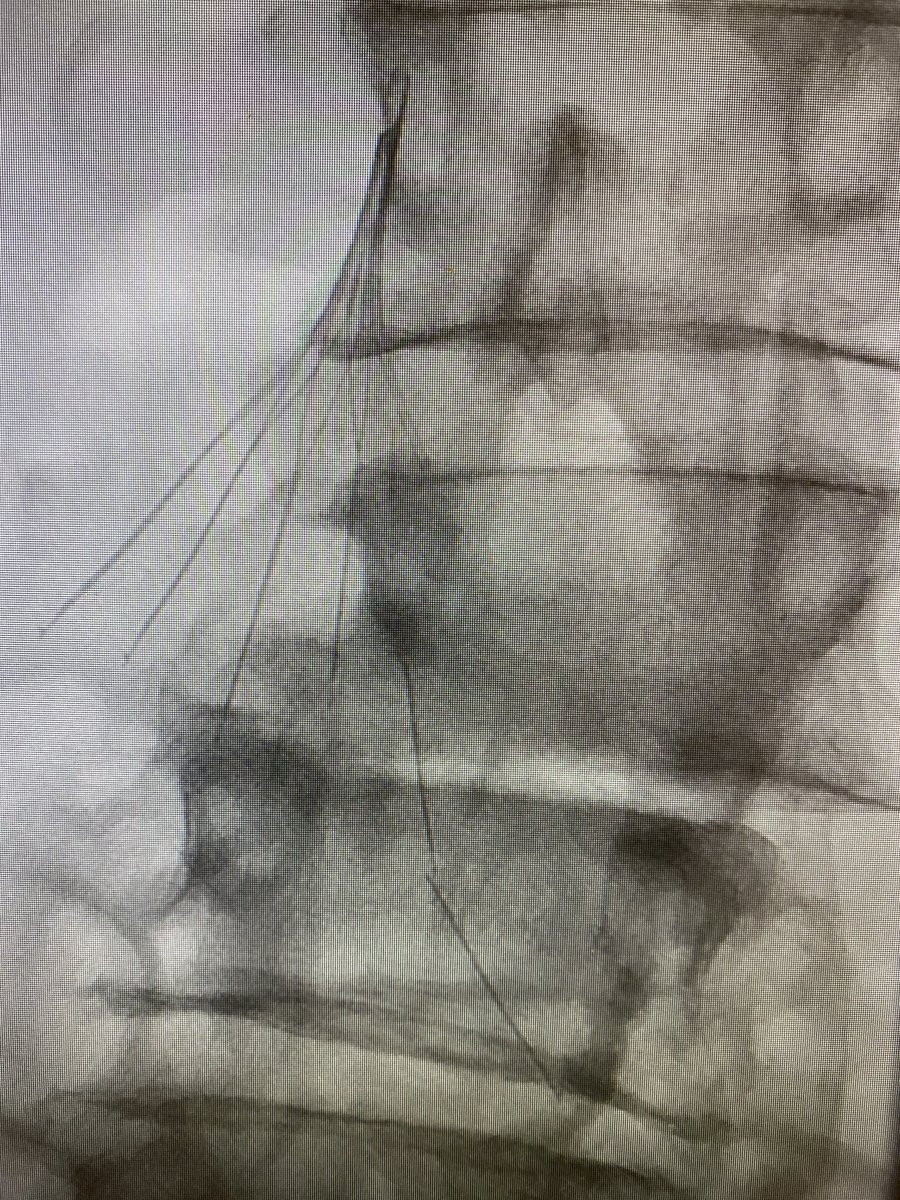

89 yo w/type 2 endoleak and growing aneurysm sac. Translumbar access followed by embolization with Onyx 34. #IRad #Onyx #endoleak @SIRRFS @SIRspecialists @GESTSymposium @SunilNarayanMD @ncdoro